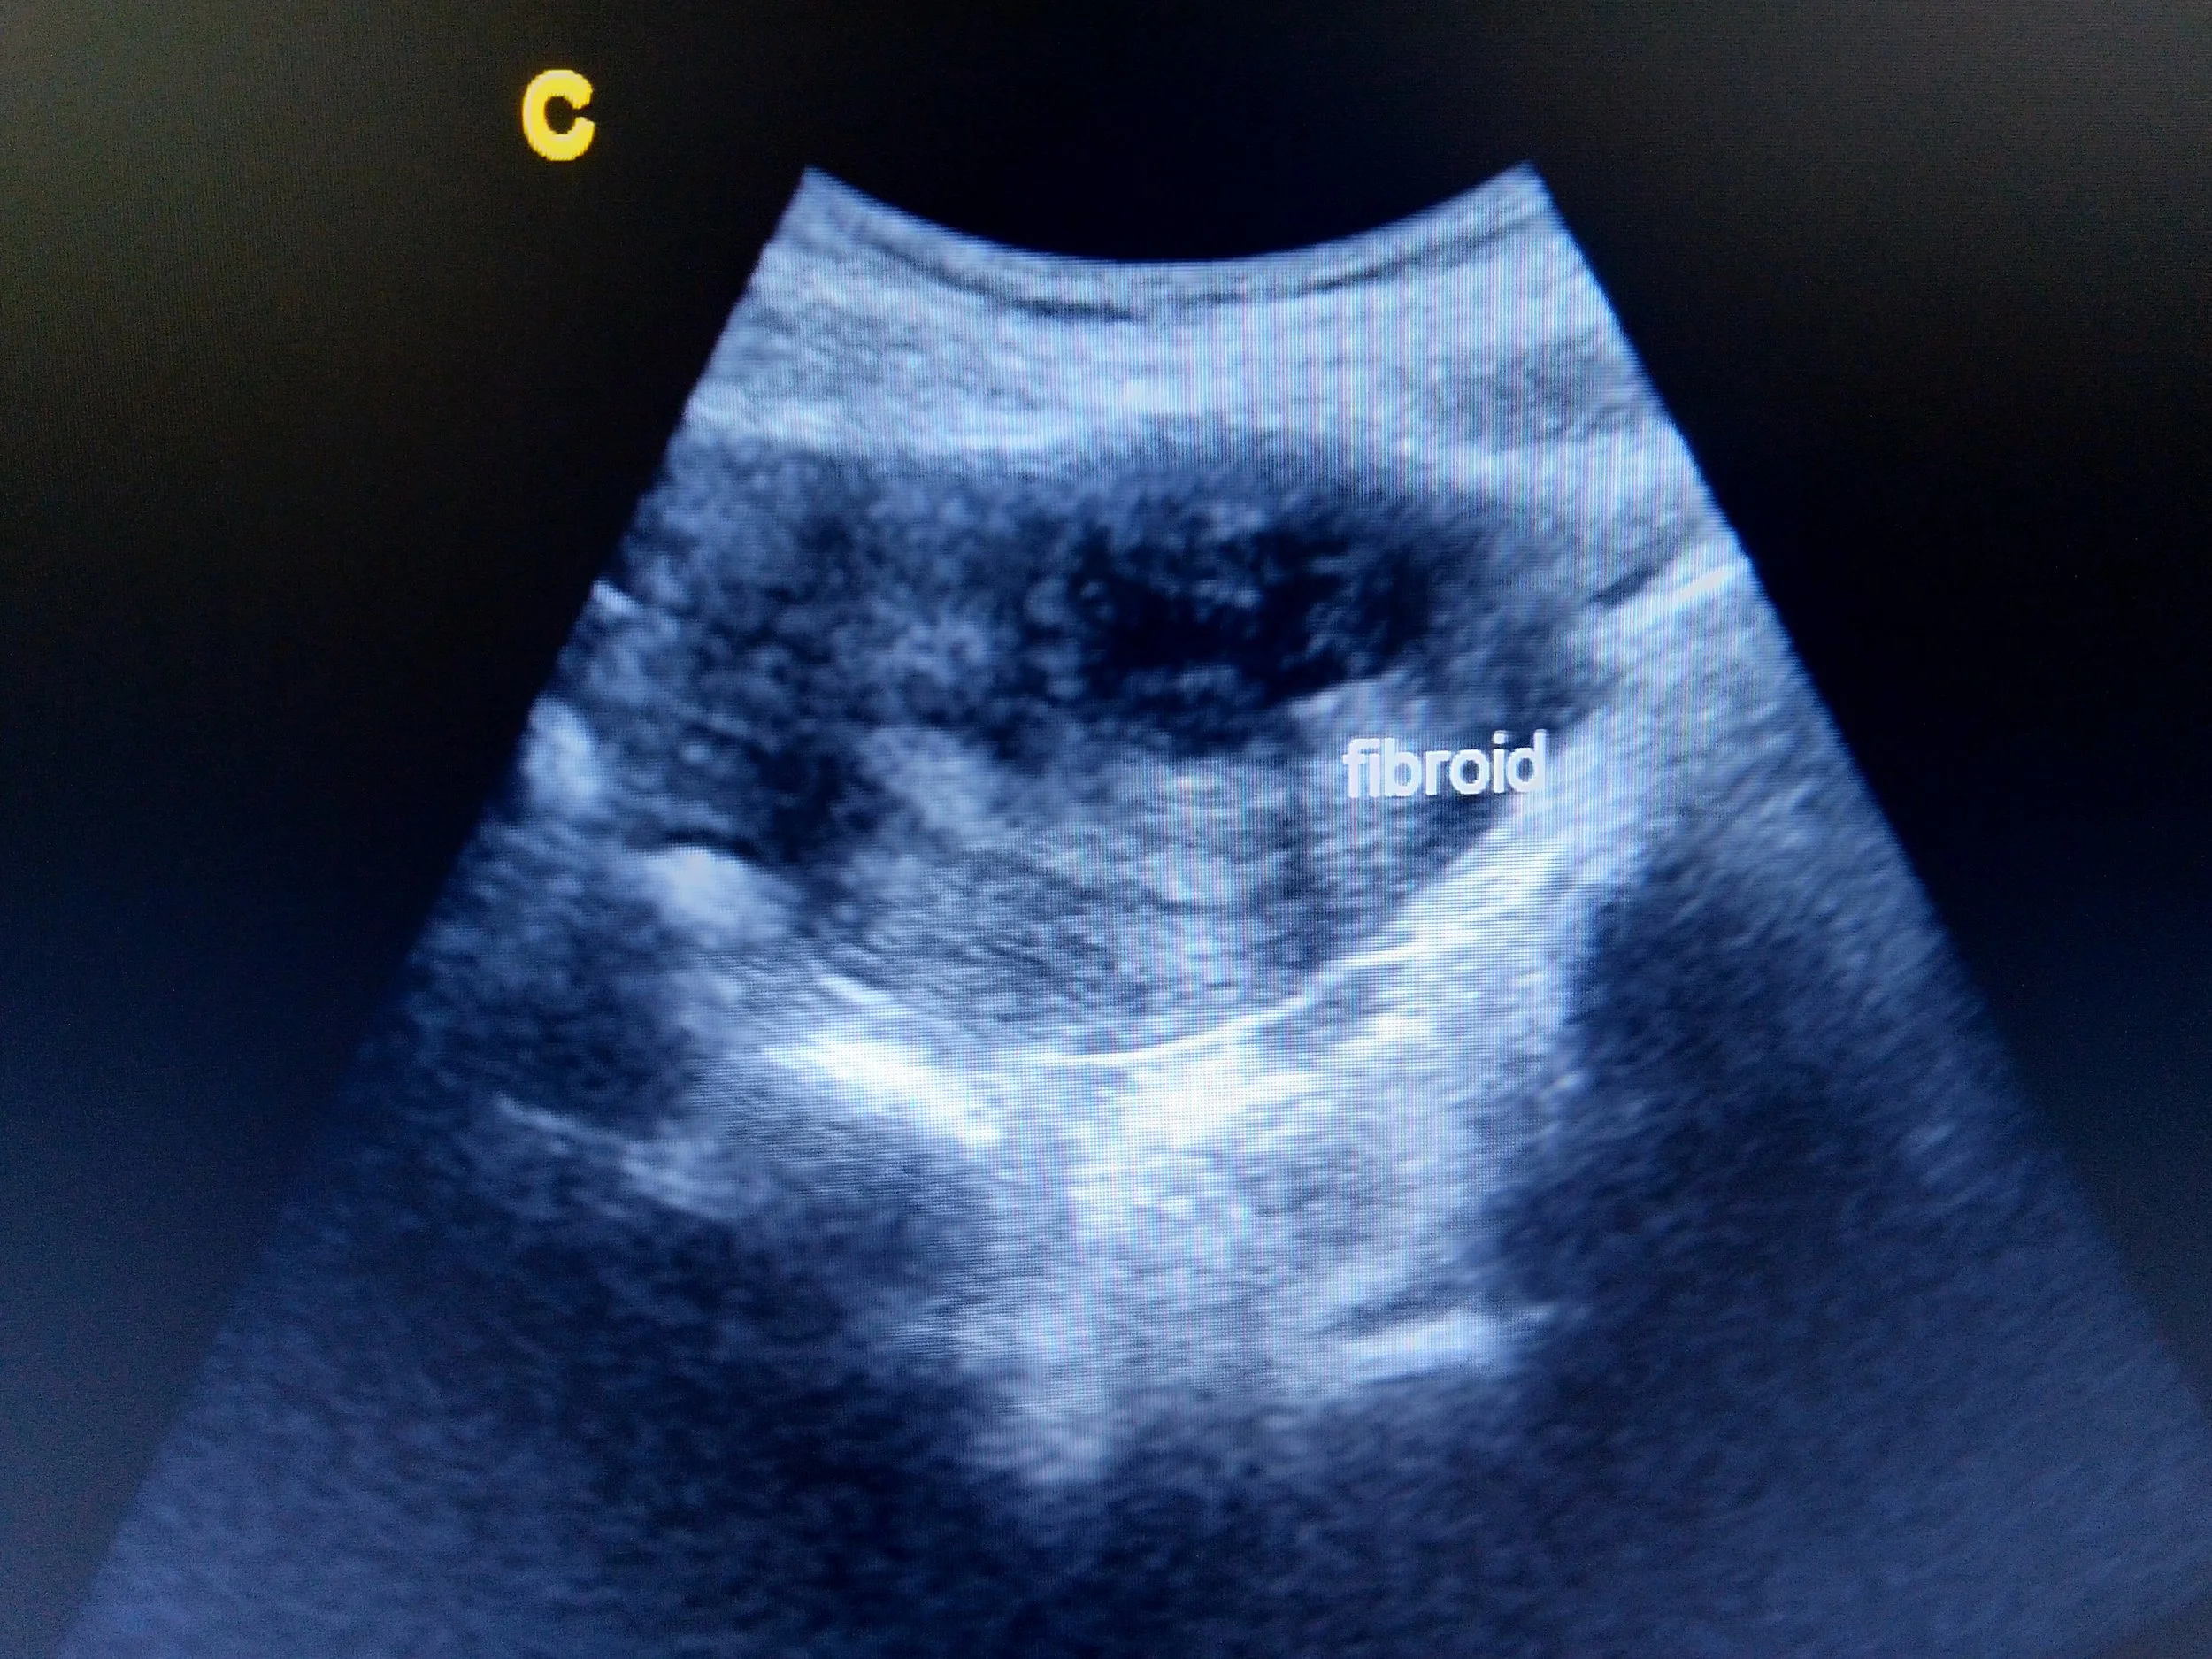

• Pelvic ultrasound: to assess your uterus

• Sonohysterogram: a specialised ultrasound which utilises fluid for clearer images inside the uterus